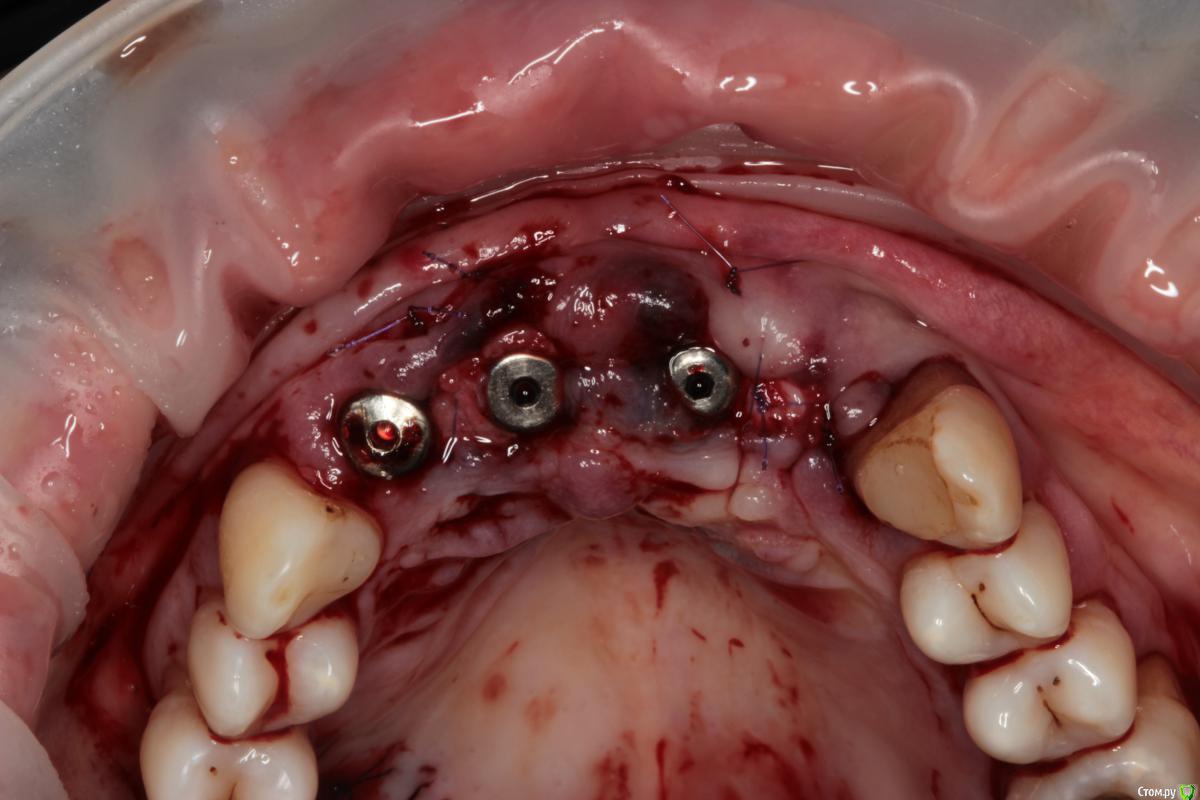

Abuk Опубликовано 27 ноября, 2015 Поделиться Опубликовано 27 ноября, 2015 (изменено) 1.bmp2.bmp3.bmp4.bmpЛечение.Альгинатные слепки,восковая моделировка.Удаление зубов и имплантата,удаление грануляций.Установка имплантатов,заполнение лунок графтом.сст,Времяхи по ключу. Изменено 27 ноября, 2015 пользователем Abuk 13 Ссылка на комментарий

Abuk Опубликовано 29 ноября, 2015 Автор Поделиться Опубликовано 29 ноября, 2015 (изменено) 1 е фото -"до", после были слепки и гигиена.Непосредственно перед имплантацией нет.Гигиена не фонтан,условились на том что первый год приходит каждые 3 месяца(осмотр и ггигиена),а там далее смотрим. Изменено 29 ноября, 2015 пользователем Abuk Ссылка на комментарий